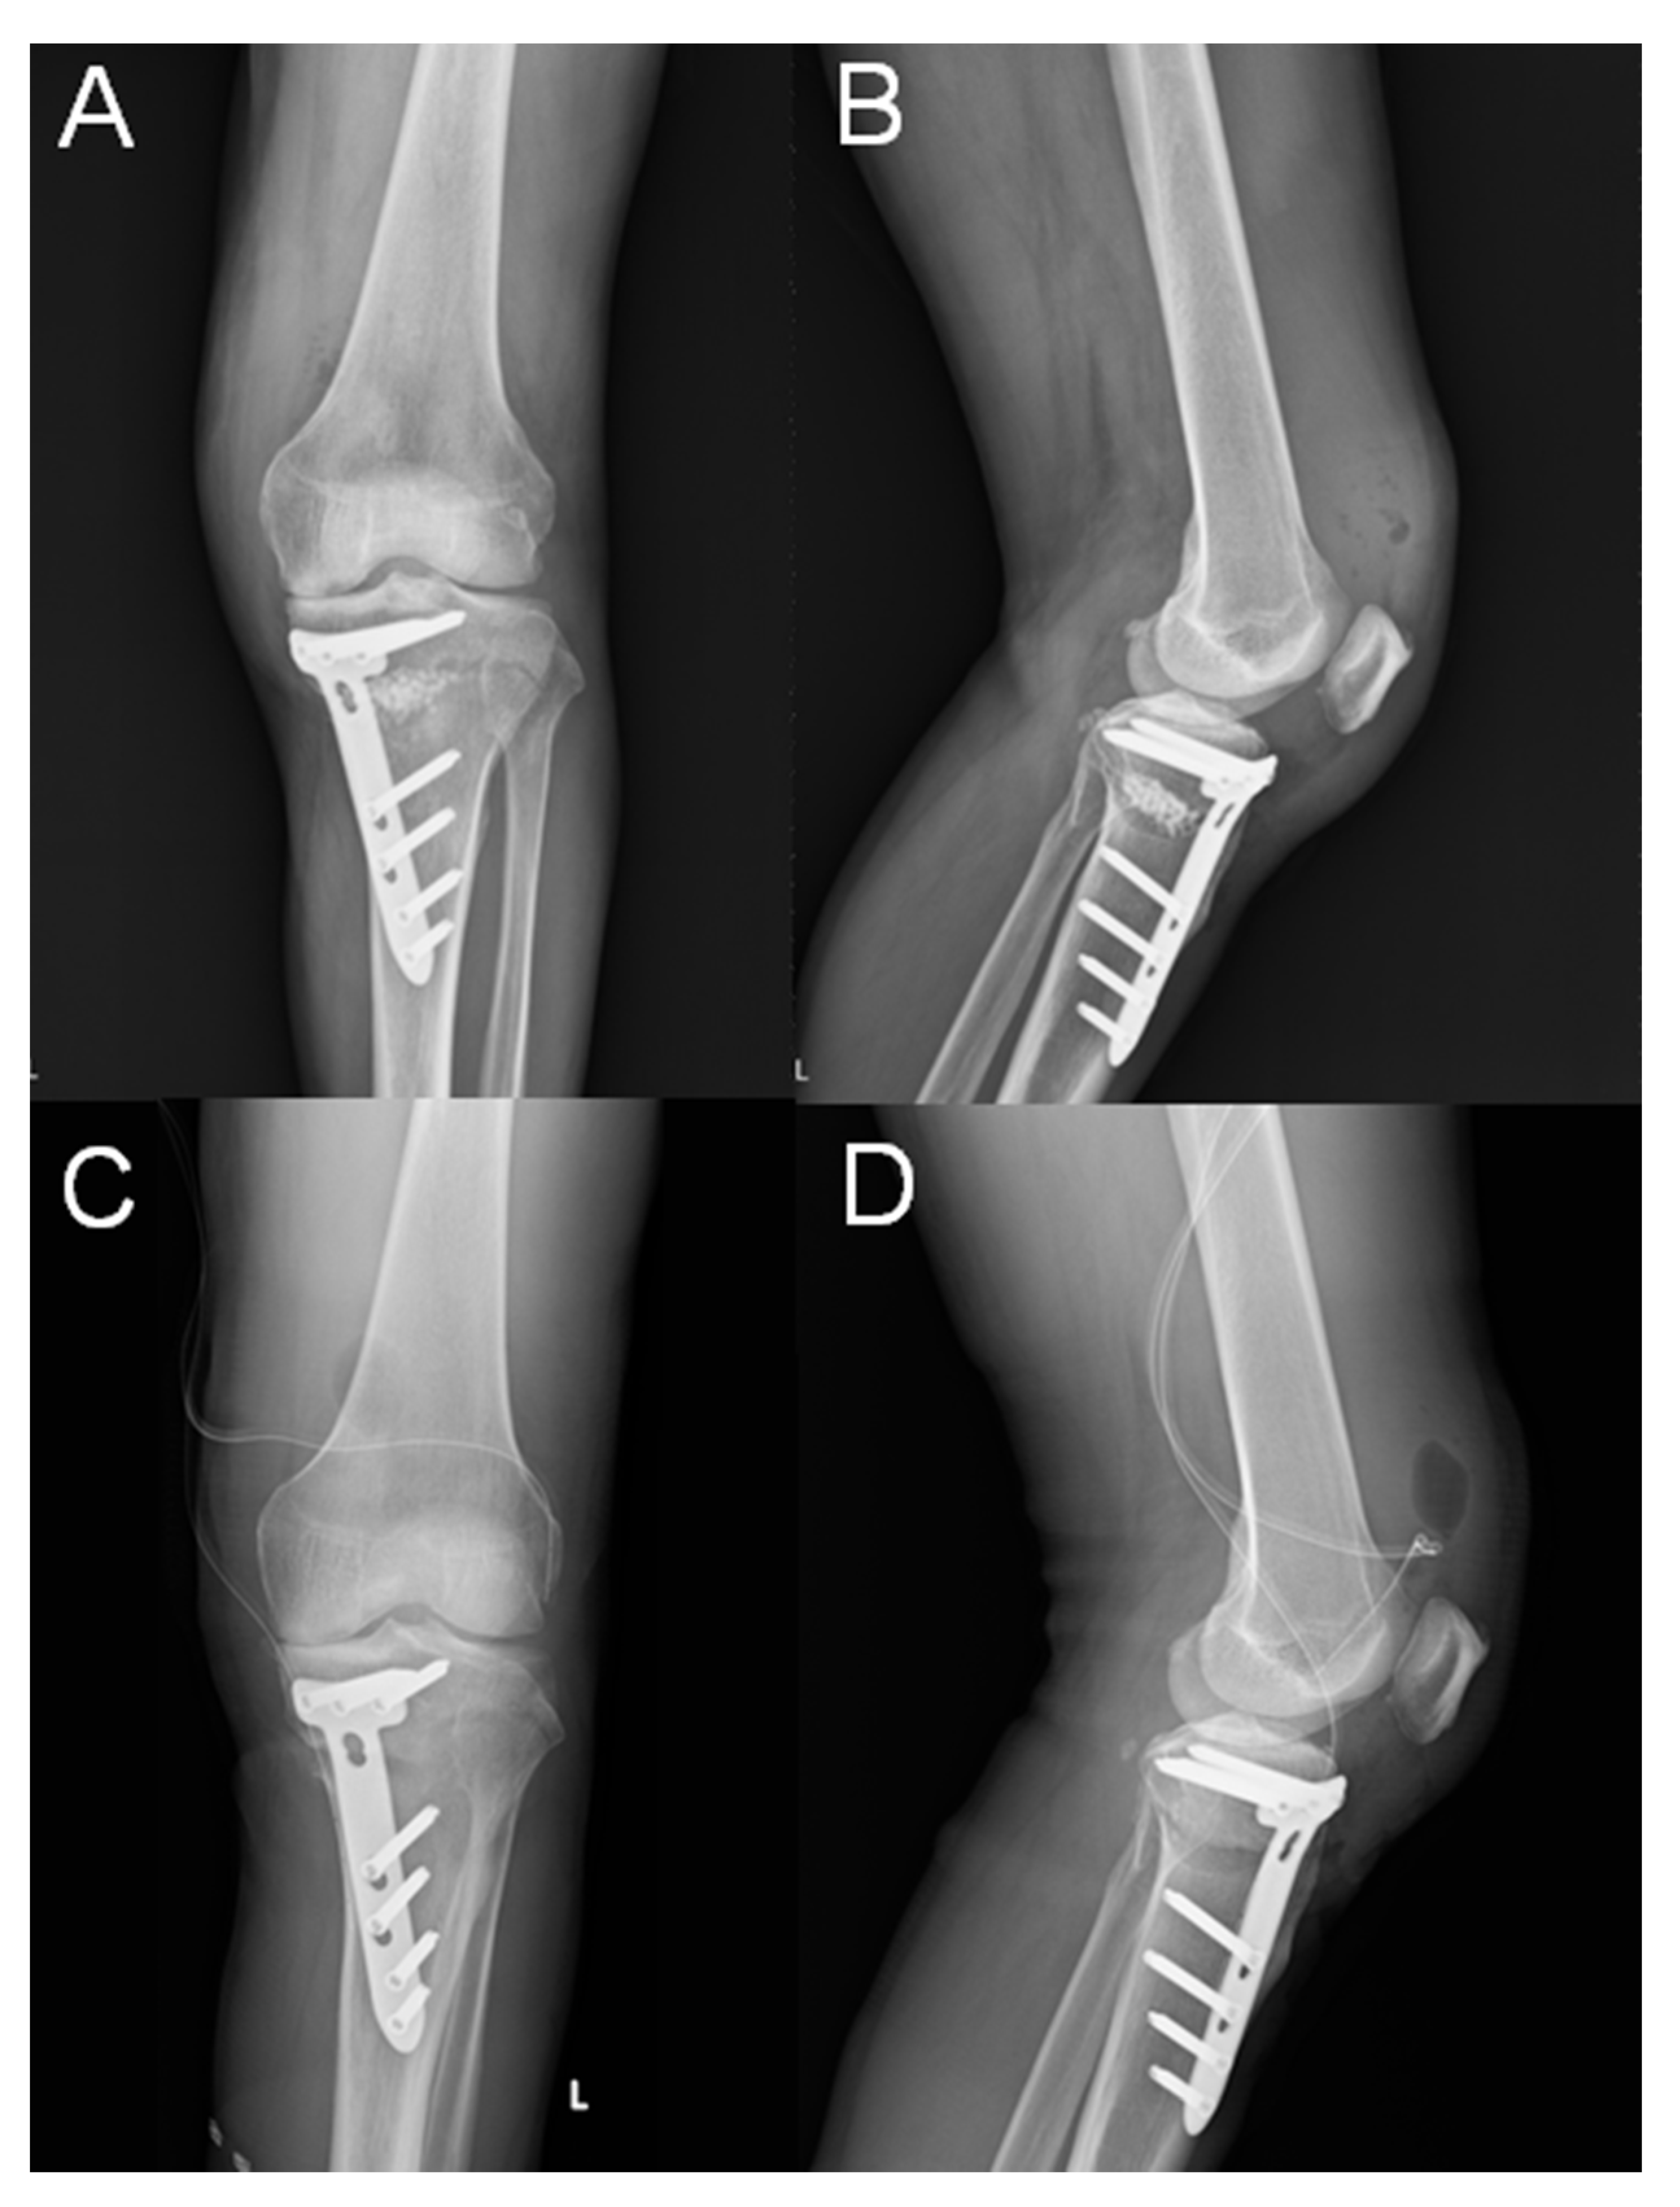

| M, 64, 25.3 | HCV | yes | 17 degree | nil | 3 months | No growth | Arthroscopic debride of knee joint, open debride of osteotomy site tics with daptomycin and Ceftazidime for a total of 6 weeks | 8 months |

| M, 58, 26.1 | Type II DM | yes | 9 degree | nil | 2 weeks | Staphylococcus epidermidis | Arthroscopic debride of knee joint, open debride of osteotomy site, systemic antibiotics with daptomycin for total of 6 weeks | 8 months |

| M, 46, 26.4 | Nil | yes | 11 degree | Lateral hinge fracture, Takeuchi type III, fixation with cannulated screws × 2 | 2 months | MSSA | Open debride of osteotomy site, systemic antibiotics with Oxaxillin for a total of 6 weeks | 8 months |